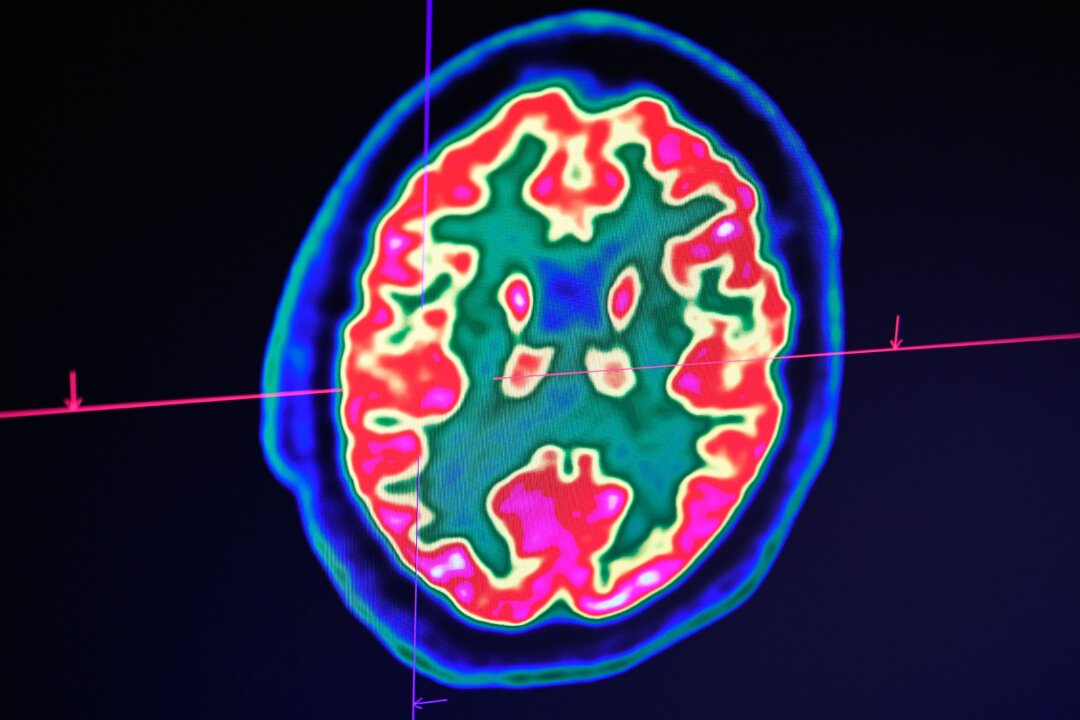

Scientists at the University of California–Riverside said in recent findings that the key to understanding Alzheimer’s may have to do with “tau” proteins that likely cause neurofibrillary tangles—which are found in the brains of Alzheimer’s patients. Previously, researchers suggested that amyloid plaques, which are a buildup of amyloid peptides, may be the cause.

Both amyloid plaques and neurofibrillary tangles are critical indicators that doctors look for when trying to diagnose Alzheimer’s…